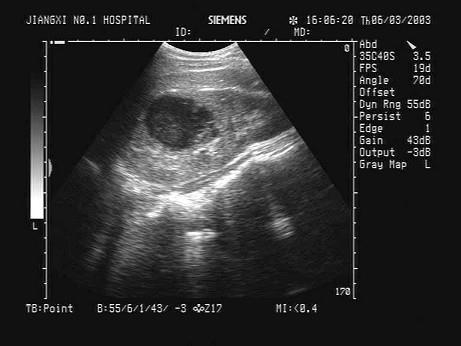

问题 某患者因左腰部疼痛不适、发热就诊,肾脏超声声像图如下,最可能的诊断为?(?)

选项 A.肾囊肿 B.急性肾炎 C.肾脓肿 D.肾癌 E.肾血肿

答案 C